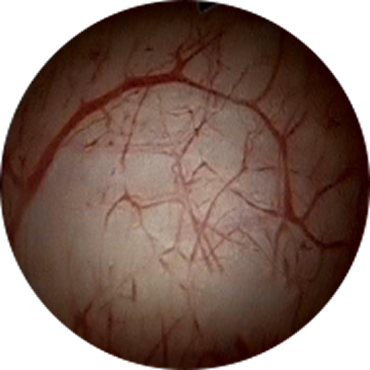

정상 방광